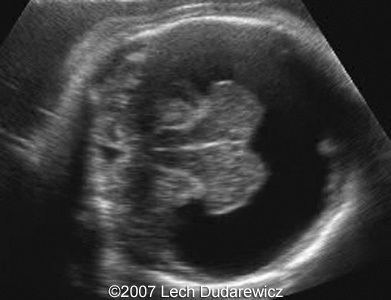

What is this an image of?

semilobar holoprosencephaly